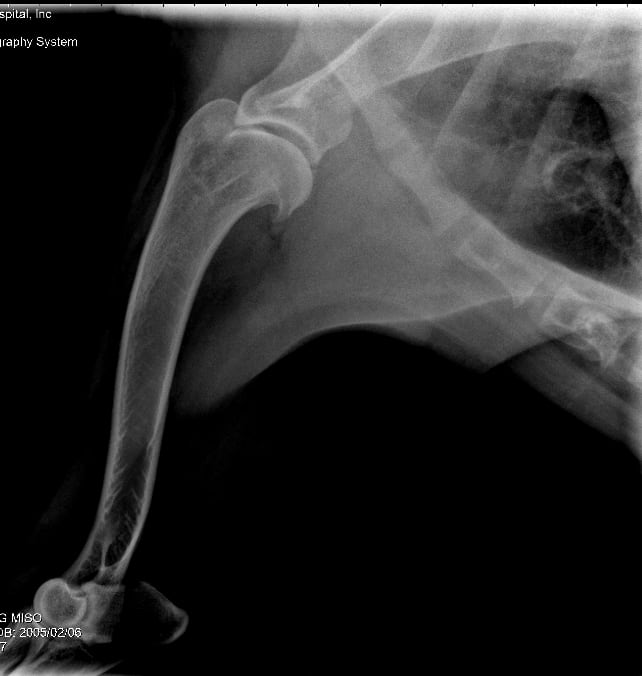

My 13-year-old Golden has a limp. Is shoulder x-ray lucency cancer?

My 13 year old Golden Retriever was seen by a vet today for a limp. Shoulder x-rays were done. There is concern about a possible osteosarcoma of the left shoulder based on an x-ray. The vet consulted with another vet and together they are not completely certain but feel that there could be a lucency in the x-ray c/w a possible tumor.

Hi. There is an abnormality in the cores of the bone near shoulder. Cancer is a possibility, along with bone infections (bacterial or fungal), or inflammatory diseases. Unfortunately with her being older, cancer is higher on the list then younger pets. Based on this xray, we can't say for sure. I would recommend sending these x-rays to a radiology specialist, which your veterinarian can do. A bone biopsy can be done as well to determine if the changes are consistent w cancer. Good luck.